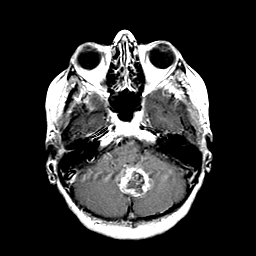

Metastatic Adenocarcinoma of the Colon: T1-weighted MR -- Slice #6

[Home][Help][Clinical] Slice 6